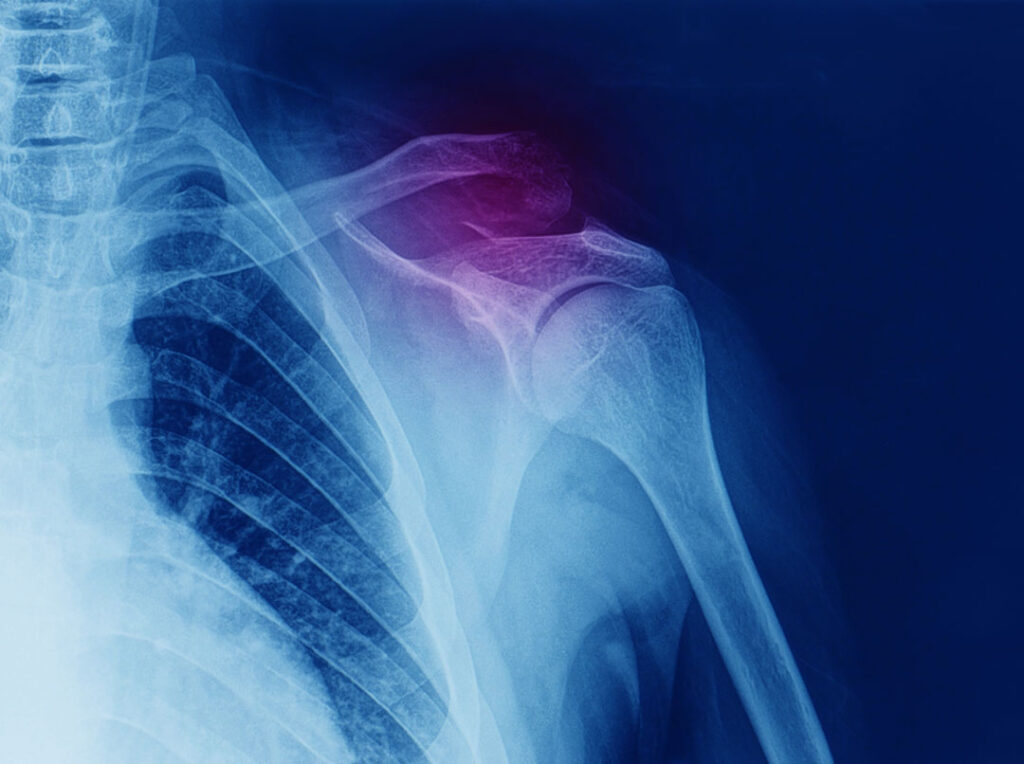

Your collarbone and shoulder blade articulate together at the acromioclavicular joint, and the coracoclavicular and acromioclavicular ligaments help stabilise the joint. These ligaments are susceptible to injury and, when sprained or torn, can cause the joint to separate.

Choosing the right therapist starts with them being able to read your X-rays, clinical assessment to determine the appropriate treatment. The therapists at Action Rehab are experienced in assessing and reading X-rays.